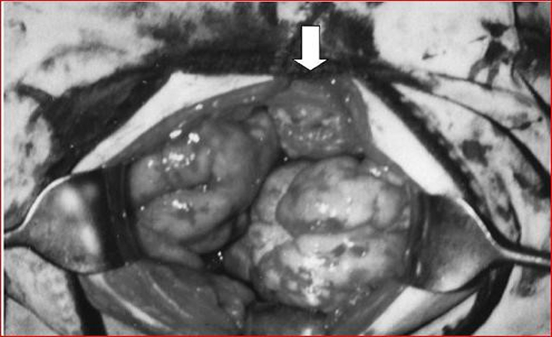

Below are the laparoscopic and MRI images (Figures 15 and 16).

Figure 15: The image shows bilateral tumor masses and omental enlargement.

Figure 16: The image highlights bilateral multi-nodular masses and some omental tumor involvement (arrows), which is visible in the lower abdominal cavity.